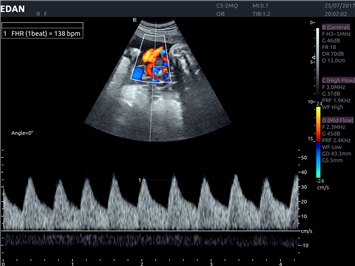

EDAN Acclarix LX4 представляет собой инновационную ультразвуковую систему, построенную на усовершенствованной платформе Acclarix. Сочетание высокого качества визуализации с интеллектуальным рабочим процессом делает эту систему оптимальным выбором для клиник, ценящих эффективность и экономичность.

• Автоматизированные измерения в акушерстве

• Акушерства и гинекологии

Общая визуализация, Гинекология и акушерство, УЗИ для кардиологии

Импульсно-волновой допплер:

Да

Постоянно-волновой допплер: